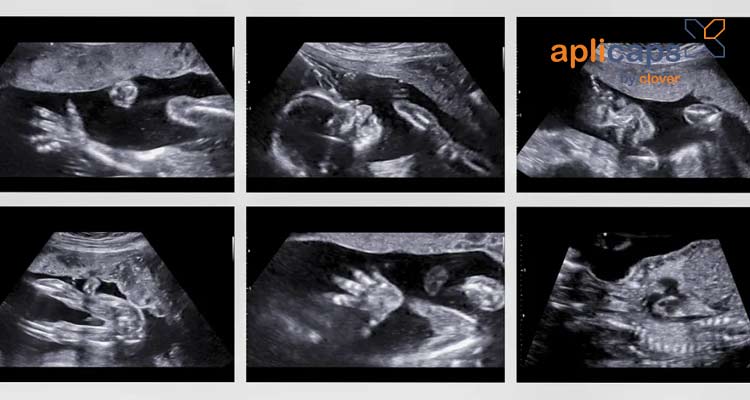

Hình ảnh siêu âm thai nhi 20 tuần khoẻ mạnh

Khi siêu âm thai ở tuần 20 mẹ có thể biết rõ hơn về em bé của mình có đang phát triển khỏe mạnh không. Bác sĩ thông qua siêu âm sẽ kiểm tra được tất cả bộ phận của thai nhi và các chỉ số cần thiết.